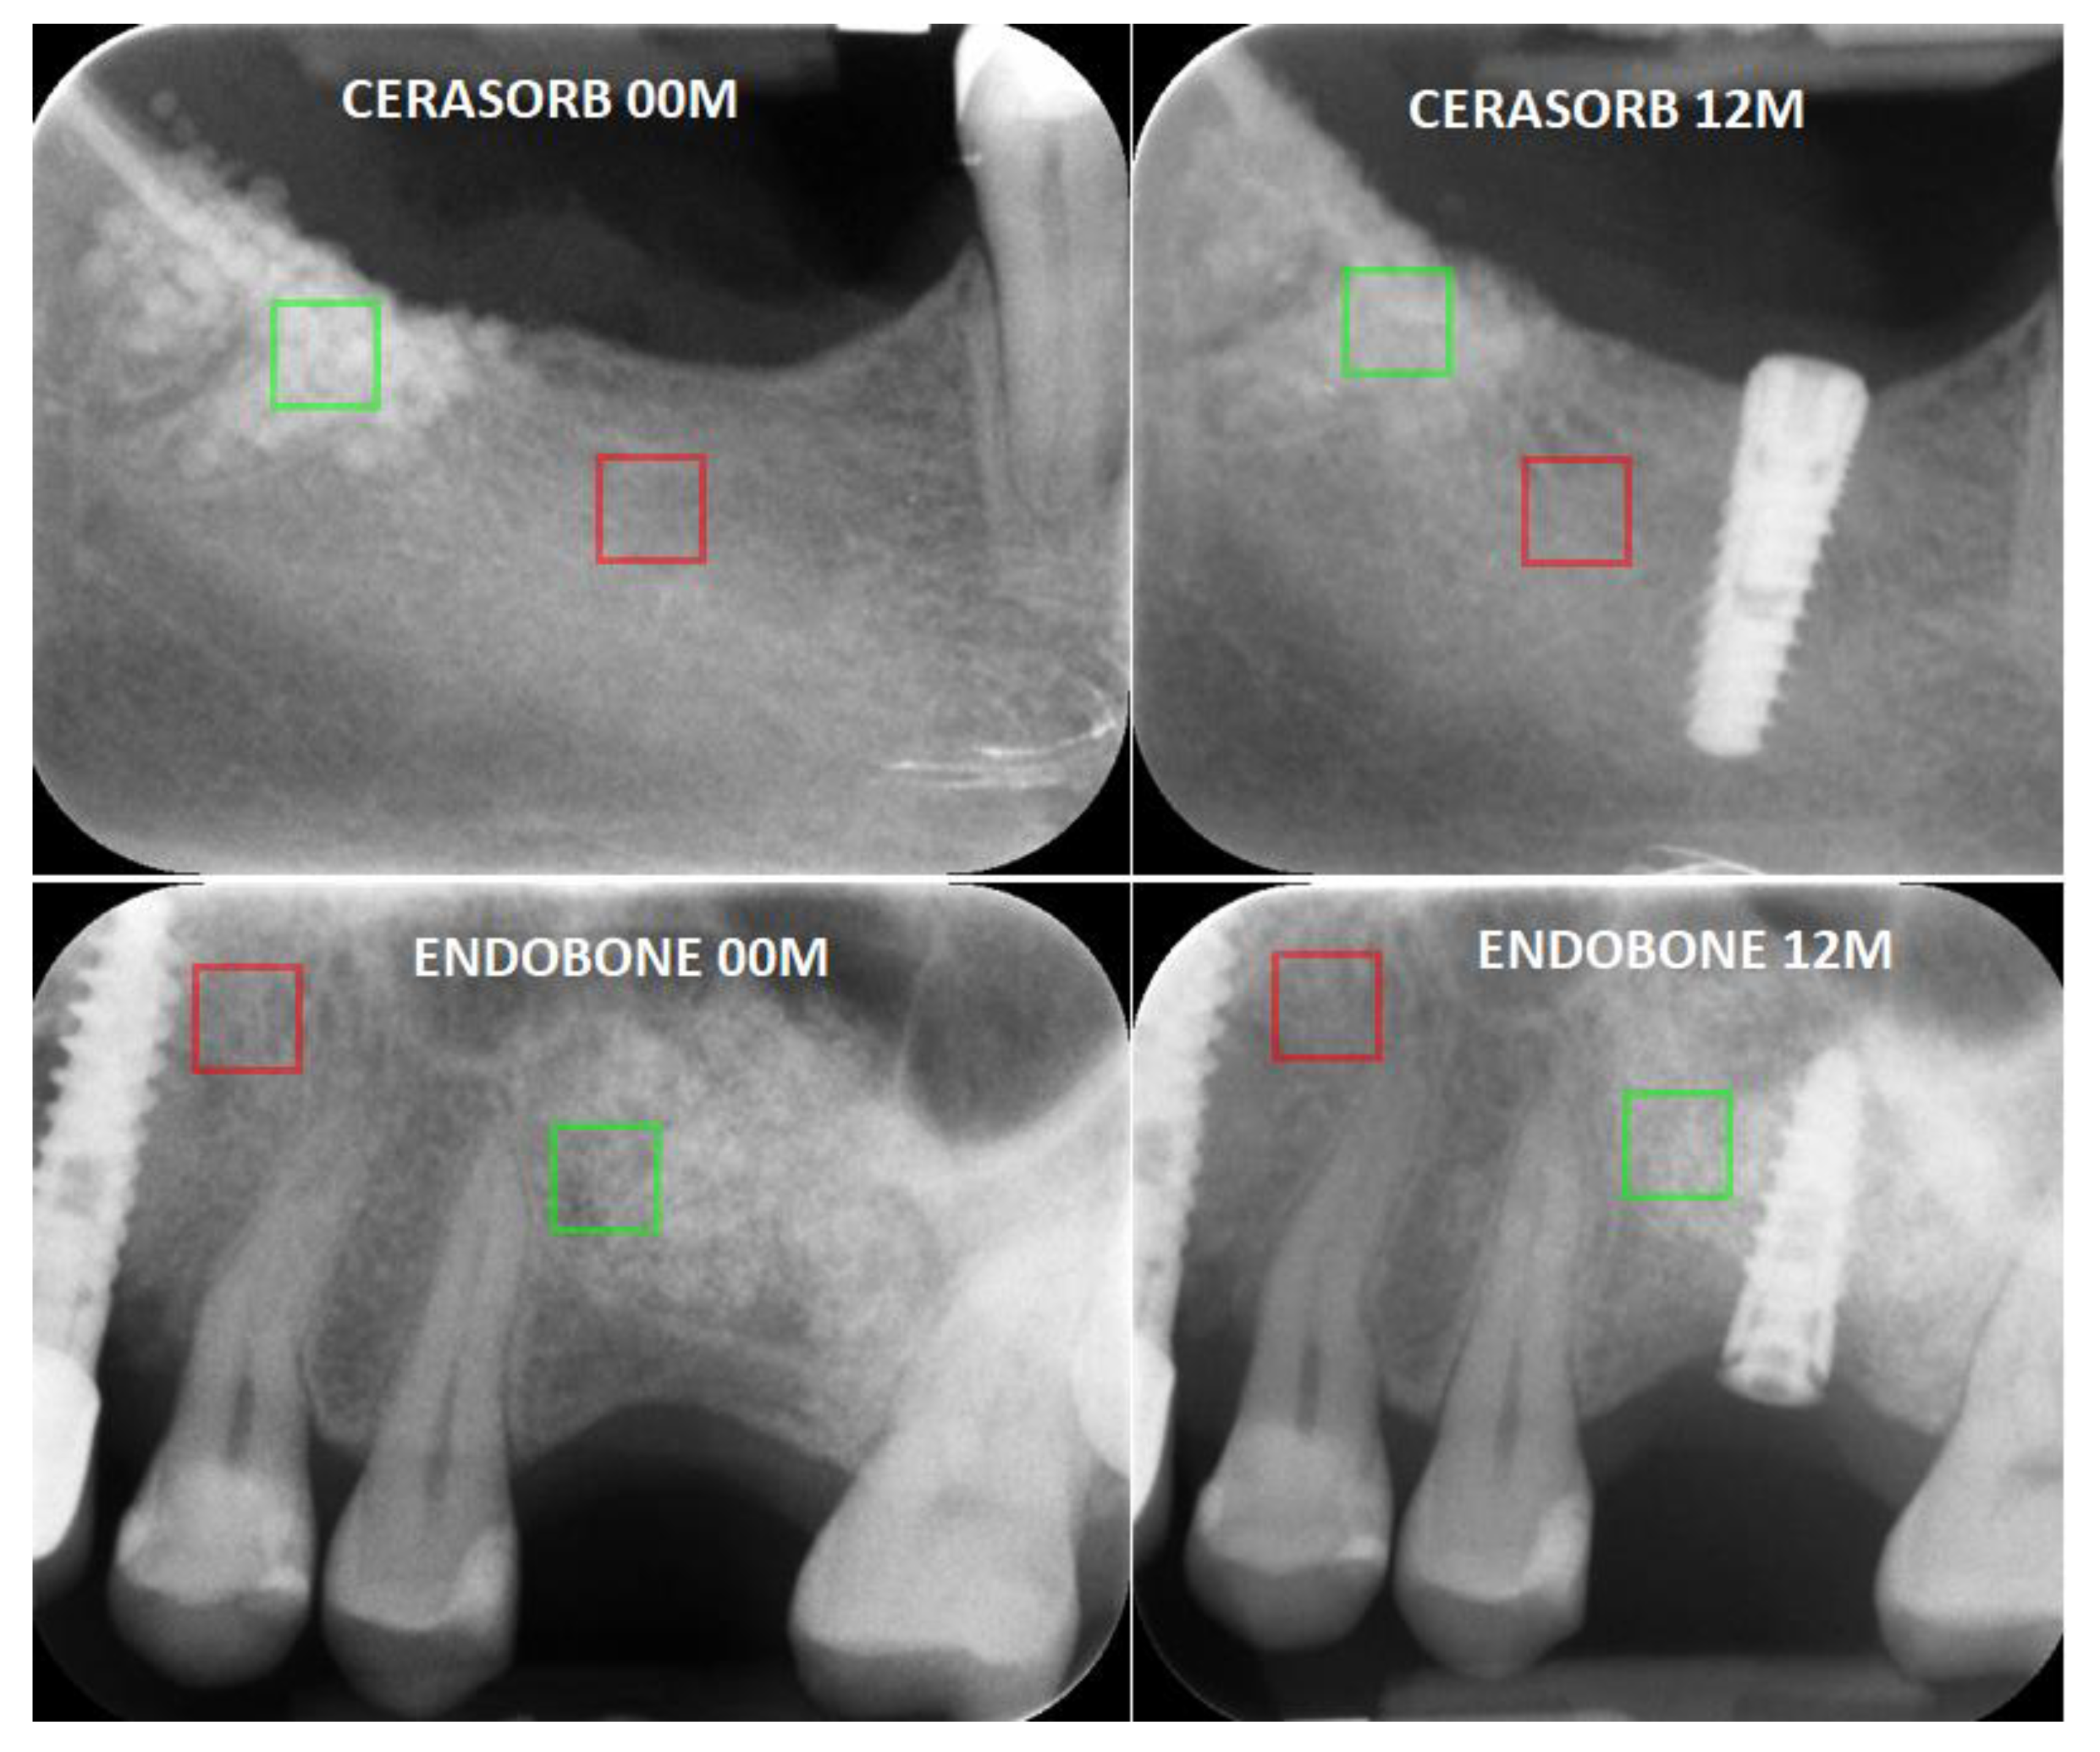

First, the X-ray image was imported to MaZda in the.bmp file format (bit map). Next, the ROIs were marked with an average of 2370 pixels for the bone area and 2541 pixels for the material area. ROIs greater than 800 pixels were found to be sufficient to perform repeatable texture analysis [13]. In all images, material texture ROIs were marked in green and reference bone ROIs were marked in red (Figure 2). The ROIs were normalised to share the same mean and standard deviation of the grey level inside the ROI (μ ± 3σ, where μ and σ denote the mean and standard deviation of the registered optical density, respectively).

Figure 2.

Examples of analysed intraoral radiographs (directly after implantation (00 M) and one year after surgery (12 M)). The exemplary regions of interest (ROI) are marked in green (material ROI) and red (bone ROI).